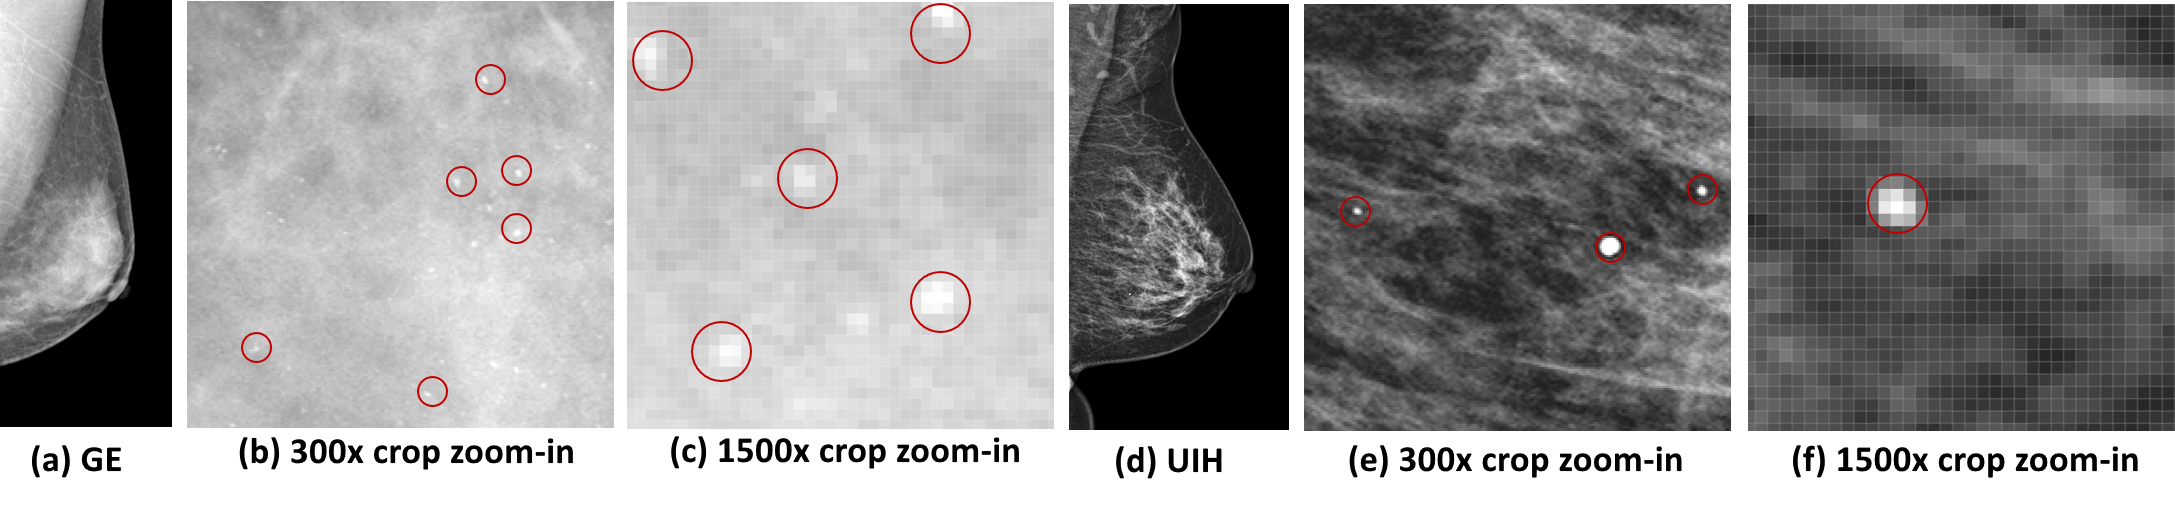

Refer to caption

Figure 1: The comparison of image styles from different vendors. Red circles highlight calcifications and μ𝜇\muCs.

The mammography is a widely used screening tool for breast cancer. It has been shown in many studies [2][5] that the incorporation of CAD softwares in the reading workflow of mammography can be helpful to improve the diagnostic workup. Equipped with the deep learning (DL) techniques, the CAD scheme was shown to further outperform radiologists from multiple centers across several western countries [7]. Although promising CAD performances for mammography have been shown in many previous studies, there is still an essential issue that is not well and explicitly addressed in previous DL works. As shown in Fig. 1, the image styles, like image contrast, edge sharpness, etc., of different vendors are quite different. Accordingly, one DL based CAD scheme may not always perform well on mammograms from different vendors, unless sufficient large and diverse training data are provided. Because the collection of large mammograms from various vendors can be very difficult and expensive, we here propose a mammographic style transfer (mST) scheme to normalize the image styles of different vendors to the same style baseline. It will be shown that style normalization step with the mST scheme can further boost the robustness of the classic Faster-RCNN detector [6] to the mammograms of different vendors and improve the detection performance for masses and microcalcification, denoted as μ𝜇\muC for short throughout this paper.

Throughout the experiments, we set the source and target domains as GE (HAsubscript𝐻𝐴H_{A}) and UIH (HBsubscript𝐻𝐵H_{B}), respectively. As can be found in Fig. 1 and Fig. 4, the image style of GE is relatively soft, whereas the UIH style is sharper. Accordingly, the image styles from different vendors can be very distinctive. We compare our method with the baselines of cycleGAN [11] and exact histogram matching (EHM)[1]. Since the cycleGAN requires training step, we randomly select 100 and 80 images from HAsubscript𝐻𝐴H_{A} and HBsubscript𝐻𝐵H_{B}, respectively, to train the cycleGAN. Except the refiner GAN, our mr2NST doesn’t need a training step. For each ST inference with mr2NST, we select 5 reference images of the target UIH domain with 5 best similar images from an reference image bank of 40 UIH images, which are not included in the 1,380 images and the 80 training data of refiner GAN. The similarity for the selection is based on the area of breast. The selected reference images are of the same view (CC/MLO) with the source image to be transferred. The optimizer Adam is adopted with 400 epochs of optimization for our mr2NST.